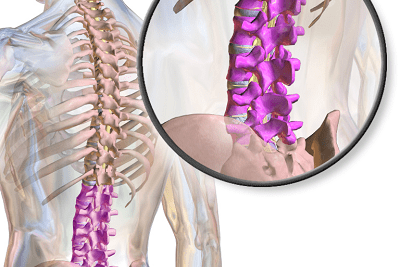

The sciatic nerve originates from the spine, running the length of the leg from buttocks to toes. It’s responsible for sensation and controlling the posterior aspect of the legs including the hamstrings, calves and bottom of the feet.

If the nerve is impinged at any point, it can cause discomfort, tingling, numbness or weakness anywhere down the back of the leg from glutes to toes.

Sciatica is typically the result of a pinched nerve in the lower back; the nerve may be compressed within or adjacent to the spinal canal as it enters the leg.

- A herniated lumbar disc; this is the most common cause of sciatica, it happens when the herniated disc puts pressure on the sciatic nerve

- Spinal stenosis; essentially a narrowing of the intervertebral foramen (the hole the nerve comes out), which places pressure on the sciatic nerve